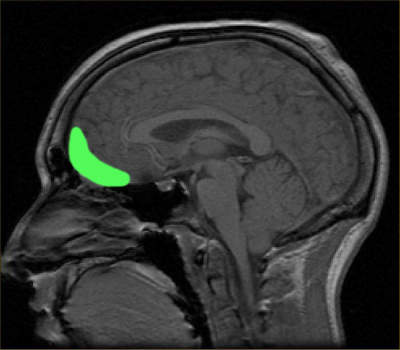

Scientists know that the orbitofrontal cortex, a region of the brain behind and above the eyes, plays a key role in making decisions. Patients with injuries to this part of the brain are often spectacularly bad at making decisions. They may do things like abandon longstanding relationships, gamble away money or lose it to swindlers, or become addicted to drugs.

In a new analysis of data from the original experiment, Padoa-Schioppa showed that different groups of cells in the orbitofrontal cortex reflect different stages of the decision-making process.

“Some neurons encode the value of individual drinks; other neurons encode the choice outcome in a binary way ‒ these cells are either firing or silent depending on the chosen drink,” he explained. “Yet other neurons encode the value of the chosen option.”

Padoa-Schioppa then examined how different groups of cells determine decisions between options of equal value. He showed that toss-up decisions seemed to depend on changes in the initial state of the network of neurons in the orbitofrontal cortex.